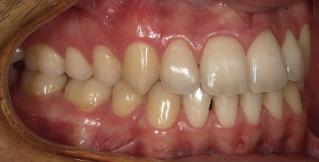

Dental Tribune Bulgarian Edition / октомври 2022 г.16 клиничен случай с алайнери Г орният латерален ре зец е вторият найчесто вродено липсващ зъб.1,2 Поради разполо жението му във видимата зона на усмивката лечение то на подобни случаи нала га мултидисциплинарен под ход, целящ отличен функцио нален и естетичен резултат. Налице са няколко лечебни мо далности, свързани с различ но разпределение на място то: първият вариант е орто донтско отваряне на място и възстановяване на липсва щия зъб с конструкция, под държана от съседните зъби3 или от имплант4, докато при втория подход разстоянията се затварят и премоларът заема мястото на канина.5 Изборът на лечебен подход трябва да бъде направен съв местно от зъболекар и паци ент въз основа на очакванията на последния и предвиди мостта на лечението. Множе ство фактори влияят върху това решение, като напри мер типа малоклузия, размера, формата и цвета на кучеш ките зъби6, оклузалните вза имоотношения (овърджет и овърбайт), лицевия профил, дължината на зъбната дъга и несъответствията в разме ра на зъбите.7 В настоящата публикация се разглежда случаят на жена в зряла възраст с вродена лип са на горен ляв латерален резец. Бяха приложени про зрачни алайнери за отваряне на място за единичен им плант и бяха постигна ти функционална оклузия и отлична естетика. ПРЕДСТАВЯНЕ НА СЛУЧАЯ Диагноза Пациентката бе на 32 годи ни, когато лечението започна, и първоначалното ѝ състоя ние бе следното (фиг. 1–3): липсващ горен ляв латерален резец; клас II, подклас I малоклузия; отклонение на горната сре динна линия вляво; Доклад на клиничен случай ЛЕЧЕНИЕ С АЛАЙНЕРИ НА ПАЦИЕНТ С АГЕНЕЗИЯ НА ЛАТЕРАЛЕН РЕЗЕЦ Д-р Iro Eleftheriadi и д-р Christodoulos Laspos, Гърция и Кипър Фиг. 1a–h Предоперативни лицеви и интраорални снимки. Фиг. 2a–e Дигитални модели преди началото на лечението. Фиг. 3 Панорамна снимка преди лечението. Фиг. 1a Фиг. 1d Фиг. 1f Фиг. 2a Фиг. 2d Фиг. 2b Фиг. 2e Фиг. 3 Фиг. 2c Фиг. 1b Фиг. 1e Фиг. 1g Фиг. 1h Фиг. 1c

Dental Tribune Bulgarian Edition / октомври 2022 г. 17клиничен случай с алайнери леко струпване в долната че люст; несъответствие по Болтън (мандибуларен излишък от 3.06 мм във фронталната зона и общо 1.47 мм); издължено лице с лицева аси метрия; конвексен профил с ретруди рана долна челюст и проми нентен нос. На мястото на зъб #46 бе на лице имплант, а зъби #16 и 26 са ендодонтски лекувани. Тези зъби бяха асимптоматич ни, затова бе взето решение да се прави релечение само при нужда. Мъдреците липсваха. Анализът на телерентгеногра фията (фиг. 4) показа ретрог натна мандибула (SNB: 74.2°) и нормална инклинация на резците както в

Цели на лечението и лечебен план Целите на лечението бяха следните: нивелиране и подреждане на зъбите и в двете зъбни дъги; отваряне на пространство за липсващия латерален резец; коригиране на отношенията при канините и моларите до клас I; и корекция на отклонението на срединната линия. Лечебният план включваше: корекция на отношенията при кучешките зъби и мола рите до клас I с дистализира не на максилата; отваряне на пространство в областта на #22 за поставя не на единичен имплант; корекция на срединната ли ния; и създаване на място за раз ширяване на зъб #12 и апрок симална редукция в долната челюст с цел подобряване на несъответствието по Болтън и осигуряване на подобра оклузия. Изпълнение на лечебния план Този случай бе изпълнен със системата за алайнери Invisalign (Align Technology). Одобреният първоначален лечебен план предвиждаше 49 алайне ра с дистализиране на задни те горни зъби до клас I (прибли зително с около 3.5 мм; фиг. 5). За бъдещия имплант в областта на липсващия латерал бе планирано пространство от 6.5 мм, докато във фронталния сегмент на долната челюст бе предвидена апроксимална редук ция. В дясната страна бутон за ластици клас II бе поставен на зъб #47 вместо на зъб #46, за да не се увреди короната на импланта. Понеже пациентката жи вееше в чужбина,

следните казуси: недобра оклу зия в дисталните зони по вре ме на дистализирането на гор ната челюст и накланяне на зъб #21 (фиг. 7). Последното се дължи на липсата на компози тен атачмънт на този зъб, каквото не бе зададено в пър Фиг. 4 Телерентгенография и цефалометричен анализ преди началото на лечението. Фиг. 5a–e Одобреният първоначален лечебен план. Фиг. 6a–h Снимки по време на лечението, показващи нуждата от внасяне на някои корекции. Фиг. 4 Фиг. 5a Фиг. 5d Фиг. 6a Фиг. 6d Фиг. 6f Фиг. 6b Фиг. 6e Фиг. 6g Фиг. 6h Фиг. 6c Фиг. 5e Фиг. 5b Фиг. 5c

планта бе поставена временна коронка (фиг. 10 и 11), докато бъде изготвена окончателна та. Бе постигнат отличен кра ен резултат. Меките тъка ни около импланта напълно заздравяха, което доприне се за перфектната хармония между бяла и розова естетика (фиг. 12–15).

Dental Tribune Bulgarian Edition / октомври 2022 г.18 воначалния план. Тези пробле ми бяха адресирани чрез допъл нителна поръчка на алайнери с торк контрол и зададено екст рудиране на задните зъби с цел установяване на добри оклузал ни контакти в дисталните об ласти, като бяха предвидени и оптимизирани атачмънти с контрол над корените за корекция на ангулацията на макси ларните резци (фиг. 8). Резултати от лечението Панорамната рентгено графия след ортодонтското лечение показа благоприятна паралелна позиция на съседни те зъби, подходяща за поставя не на имплант в областта на #22, както и конвергенция на ко рените на зъби #44 и 45 (фиг. 9), но преценихме, че няма да от деляме допълнително лечебно време за коригирането ѝ поради факта, че пациентката бе мно го доволна от постигнатия до момента резултат. След при ключване на лечението бяха постигнати отлични взаимо отношения клас I при мола рите и канините, а срединни

съвпадаха. Върху им